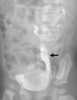

Crossed renal ectopia

Crossed dystopia (syn.unilateral fusion cross fused renal ectopia) is a rare form of renal ectopia where both kidneys are on the same side of the spine. In many cases, the two kidneys are fused together, yet retain their own vessels and ureters. [Source: Wikipedia ]